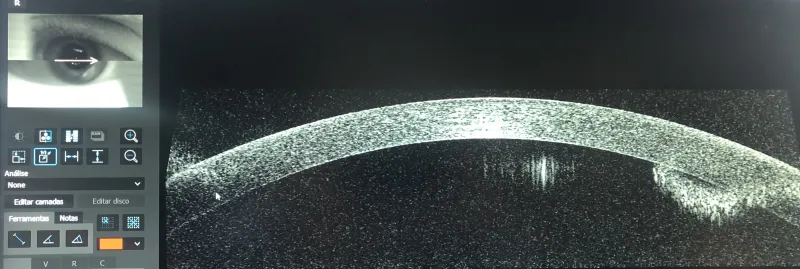

A cirurgia refrativa a laser é um procedimento indicado para corrigir erros de refração, como miopia, hipermetropia e astigmatismo.

Realizada com alta precisão, a cirurgia remodela a córnea, permitindo que a luz se concentre adequadamente na retina, melhorando significativamente a nitidez da visão.